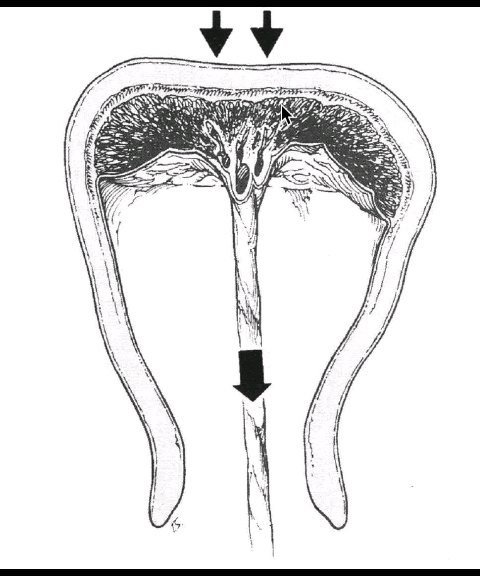

為什么胎盤出不來(lái)不能拉著臍帶往外拽?